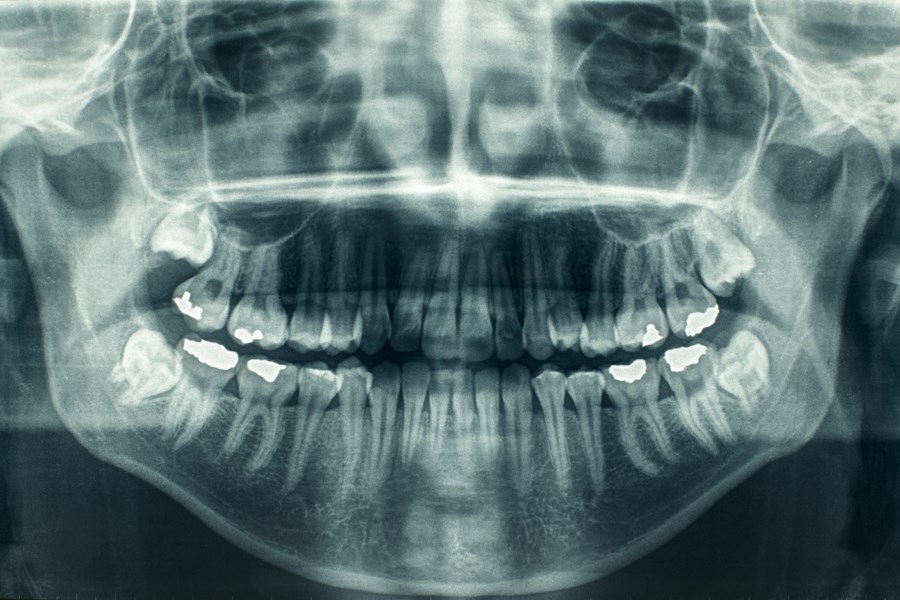

Kliniğimizde muayene ve tedavi olmak isteyen hastalarımızdan ilk önce anamnez formu alınmakta, extraoral ve intraoral klinik muayenesi yapıldıktan sonra diş hekimimizin gerekli görmesi halinde panoramic (2D) görüntüleme cihazı ile röntgen çekilmektedir.